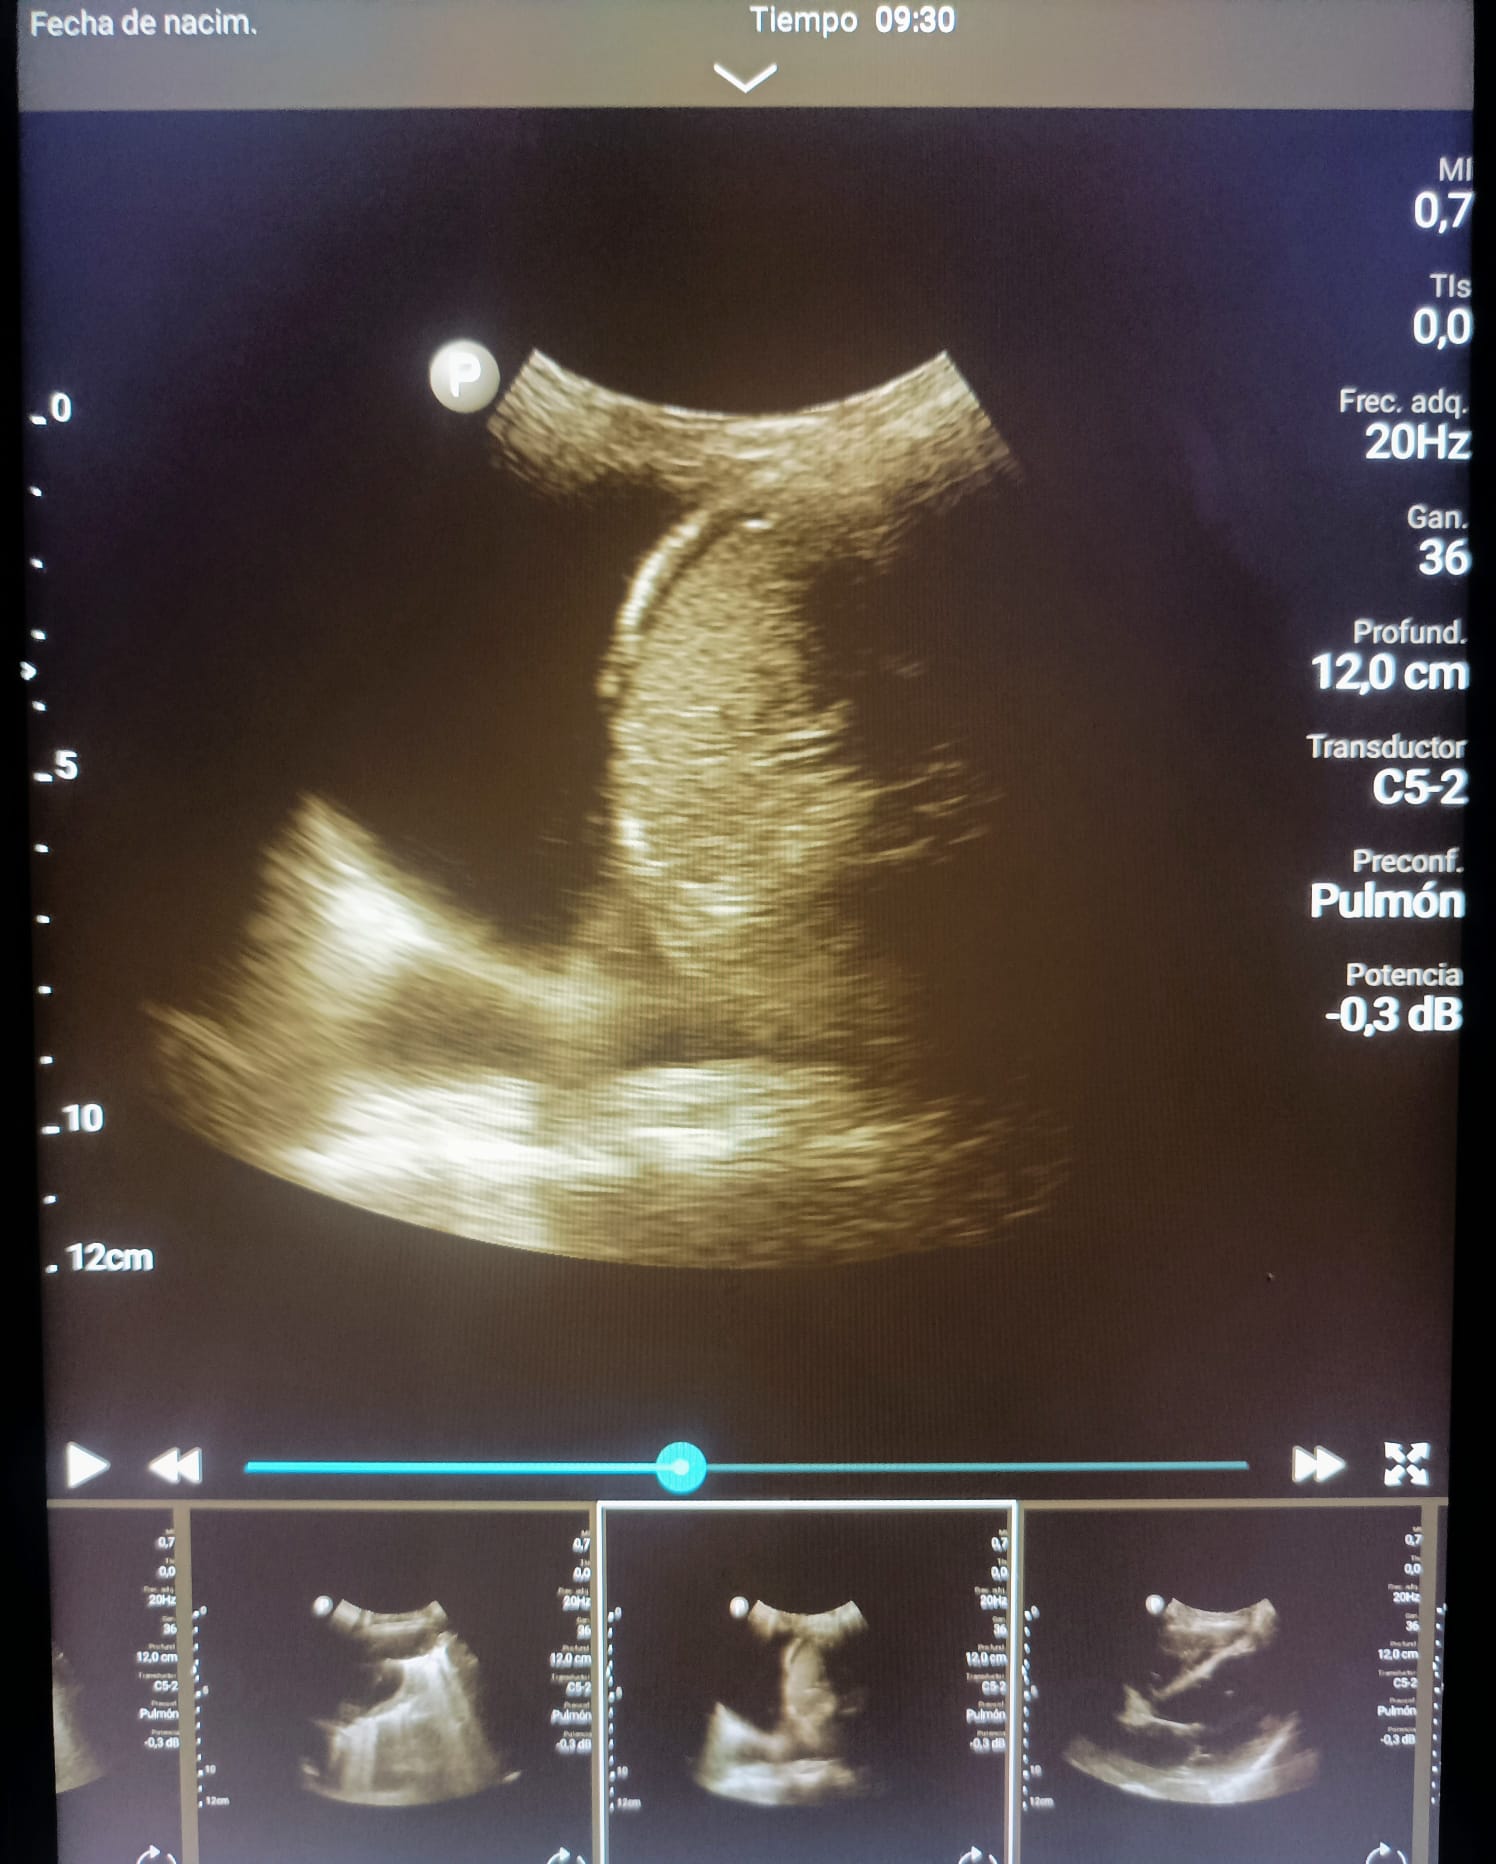

Disponíamos de una sonda convexa que nos ha permitido la realización de ecografías abdominales, pulmonares e incluso obstétricas en diferentes ámbitos; servicio de urgencias, servicio de cirugía general y medicina interna.

Las patologías mas prevalentes han sido la ascitis y la insuficiencia cardiaca, asi como pacientes politraumatizados que se han beneficiado de FAST a su entrada en urgencias.

Otras patologías diagnosticadas han sido: abscesos hepáticos, derrames pleurales, tumores hepáticos, abortos espontáneos e incluso miocardiopatía hipertrófica.

Además de diagnósticos, hemos podido realizar ciertas técnicas invasivas como paracentesis e incluso toracocentesis eco guiadas, disminuyendo asi las complicaciones secundarias a las mismas.